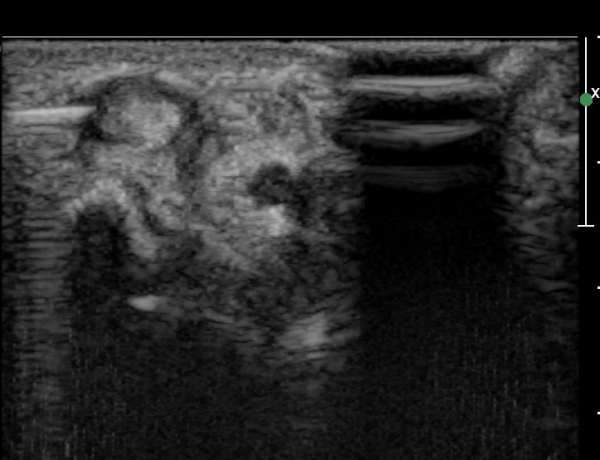

¿ä°ñ °æ»óµ¹±â ºÎÀ§¿¡¼­ tunnel I Ⱦ´Ü¸é°Ë»ç¿¡¼­ ´Ü¹«Áö½ÅÀü°Ç(EPB)ÀÇ ºÎÁ¾ ¹×

°ÇÁÖÀ§ ¼ö¾×Àú·ù°¡ °üÂûµÊ(»çÁø 1, 2)